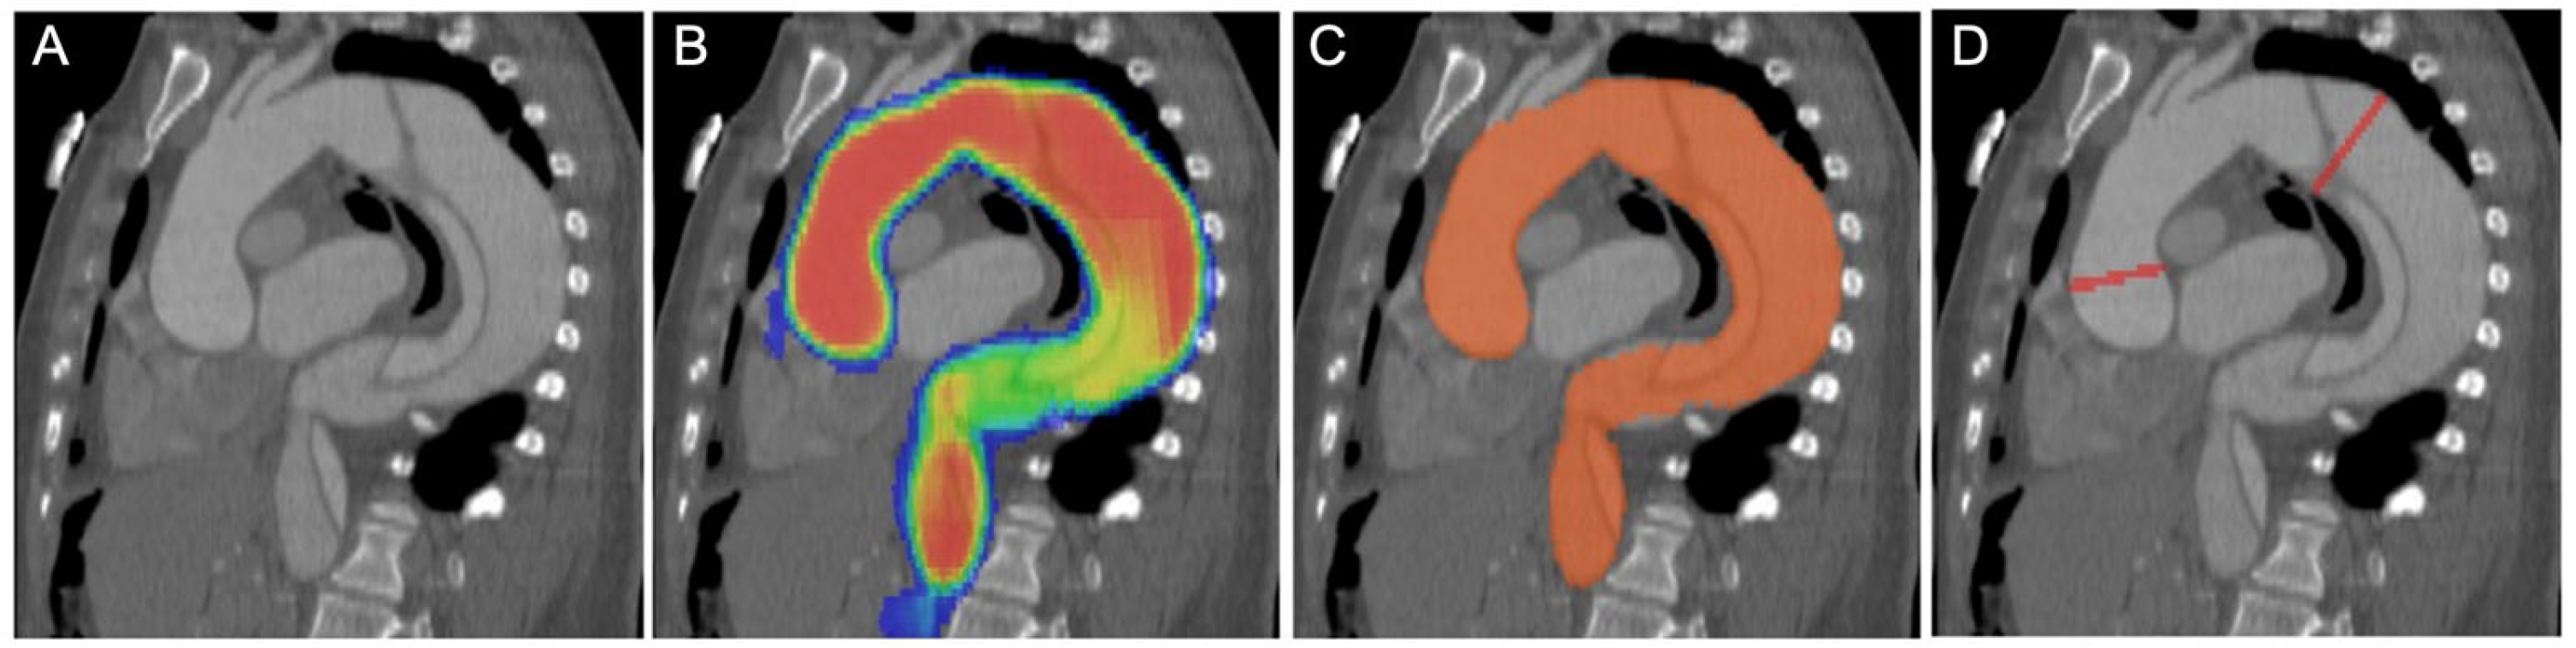

2.3. Convolutional Neural Network Model and Measurements